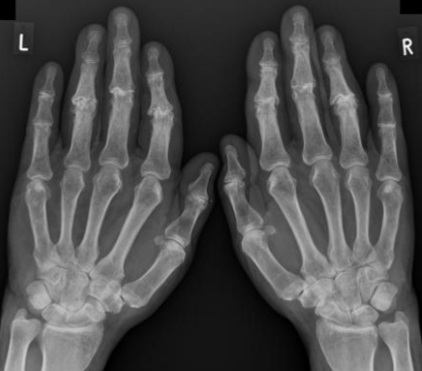

radiology - rheumatoid arthritis

affects the carpals 7 proximal joints of the hand

can widen the predentate space in the cervical spine

can lead to fusion of the posterior elements in the cervical spine